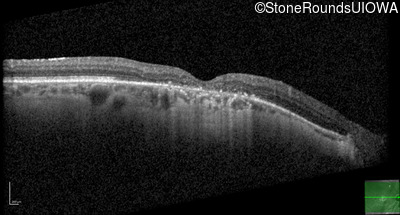

This 52 year old man had normal vision until his mid 30's when he began to have trouble distinguishing colors. the issuing 10 years he had a gradual loss of visual acuity accompanied by increasing photophobia.

| Age at visit: 55 years |

| Age at visit: 58 years |

| Age at visit: 61 years |

| Age at visit: 64 years |